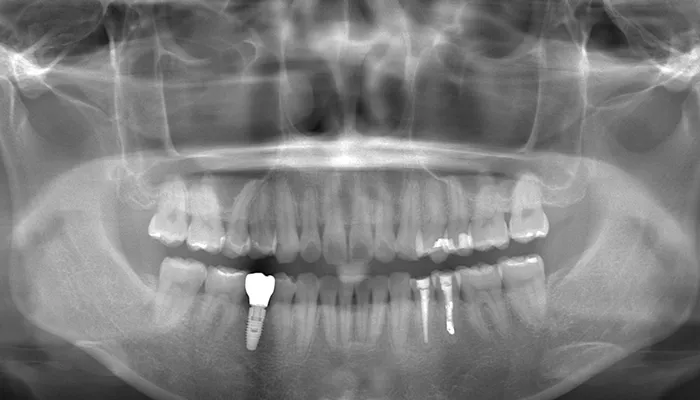

右下5番については保存不可能と判断し、抜歯を行いました。抜歯後は治癒期間を設け、十分な治癒を確認したうえでインプラントを埋入しました。オッセオインテグレーション(インプラントと骨を結合させる期間)の後、最終補綴としてジルコニアクラウンによる上部構造を装着しました。

併せて、歯列全体の叢生改善および歯の位置関係・咬合関係の改善、清掃性の向上を目的としてインビザライン矯正を行いました。治療期間中は、アタッチメントの装着やIPRを行いながら、段階的にアライナーの交換を継続しました。。

右下5番のインプラントは良好に骨結合し、自然な形態と色調の補綴物を装着しました。

インビザライン矯正により歯列が整い、清掃性・咬合バランスともに改善しました。